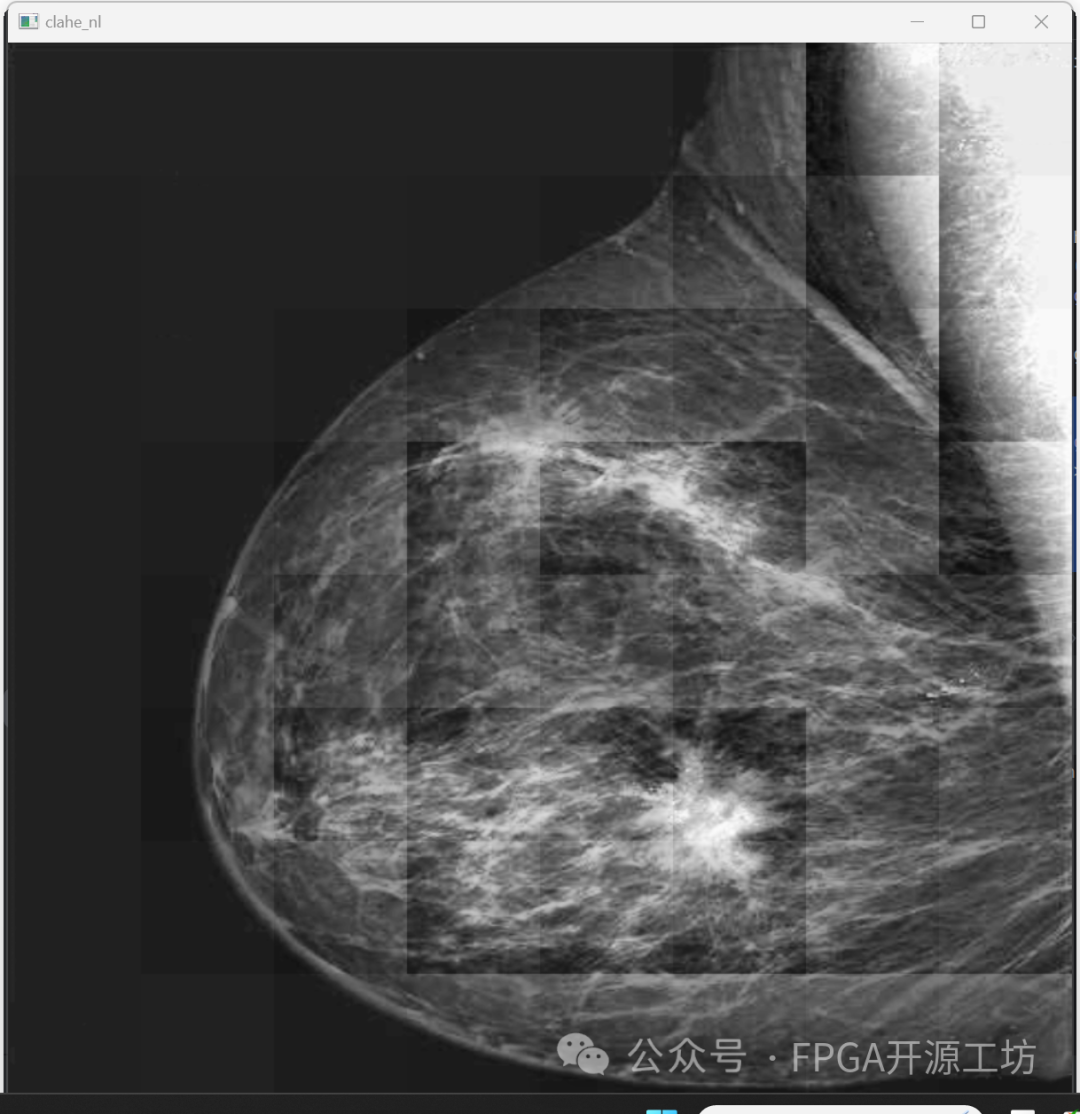

我们先来看一下没有经过线性差值的CLAHE算法是什么样子的效果。

可以看到很明显的图片中都是一块一块的,这是因为在每一个块里面都统计了相应的直方图数据,这样就导致不同块里面直方图统计的映射表不一样,所以就出现了一块块的斑点。